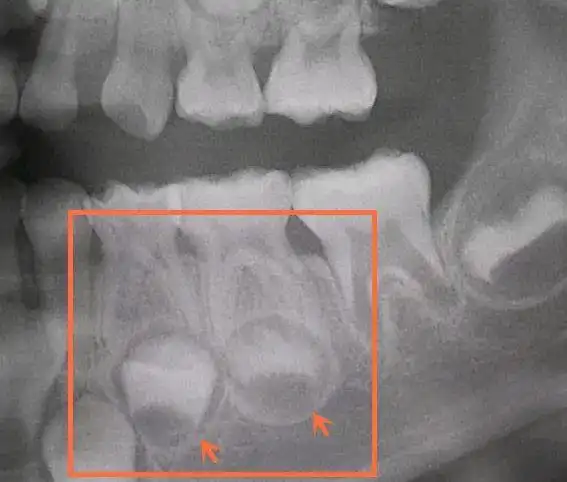

乳牙坏了真的不用管吗? - 春雨医生